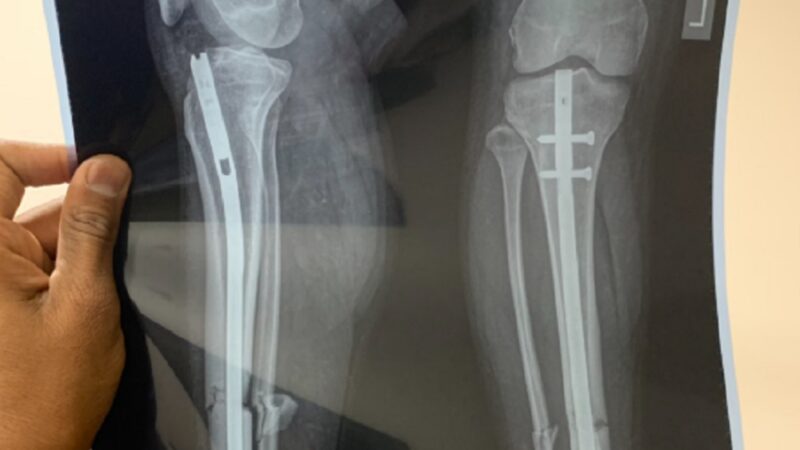

Chấn thương xương, đặc biệt gãy xương nặng, từ lâu là một thách thức đối với các bác sĩ phẫu thuật chỉnh hình. Các phương pháp truyền thống để điều…